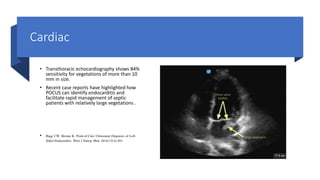

• Transthoracic echocardiography shows 84%

sensitivity for vegetations of more than 10

mm in size.

• Recent case reports have highlighted how

POCUS can identify endocarditis and

facilitate rapid management of septic

patients with relatively large vegetations .

• Bugg CW, Berona K. Point-of-Care Ultrasound Diagnosis of Left-

Sided Endocarditis. West J Emerg Med. 2016;17(3):383.